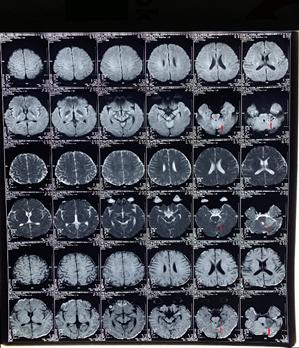

2、我院给予患者核磁共振检查(T1、T2)显示左侧桥小脑区占位性病变,结合临床考虑听神经瘤。

(MRI T1加权成像,红色指示病变区)

(MRI T2加权成像,红色指示病变区)